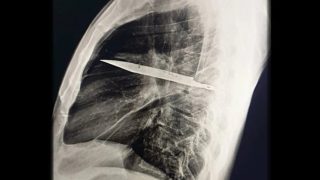

Mindig megbocsátott párjának egy bántalmazott nő, kést vágtak hozzá, és bajonettel szúrták meg végül

2022. augusztus 12-én Salman Rushdie éppen a politikai okokból üldözött írókról készült beszédet tartani New York állam egyik kisvárosában, amikor egy vallási fanatikus merényletet kísérelt meg ellene. Rushdie csodával határos módon túlélte a tizenöt késszúrást, ám maradandó sérüléseket szenvedett, többek között elvesztette jobb szeme világát is. Ennek a traumatikus eseménynek és az utána következő testi-lelki felépülésnek a krónikája a Kés című kötet. Véres a Matiné.